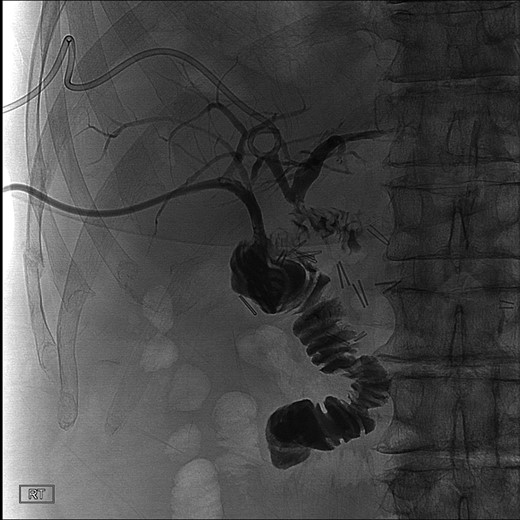

During this operation, the porta was dissected and the common and proper hepatic arteries were identified and preserved. We were unable to palpate the previously placed percutaneous biliary catheters due to the high placement above the hilum at the level of multiple clips. We transected the CBD distally and removed numerous clips, finally noting bile drainage, but were unable to identify a cholangiogram catheter. We then identified a second tubular structure more lateral to the duct. We elected to transect this tissue, identifying a second extrahepatic bile duct. The anterior percutaneous catheter was identified proximally within the duct. An on-table cholangiogram with fluoroscopy was performed noting two separate extrahepatic biliary systems, draining the right and left lobes of the liver, respectively (Figs 3 and 4). Both distal ducts were ligated to definitively close the orifice to the duodenum and prevent spillage. A Roux limb of jejunum was created and anastomosed in a retrocolic fashion to the two separate hepatic ducts at the level of the hilum. A drain was placed, and there was no evidence of bile leakage.

Intraoperative cholangiogram of the right ductal system through the extrahepatic right CBD.

Intraoperative cholangiogram of the left ductal system through the extrahepatic left CBD.